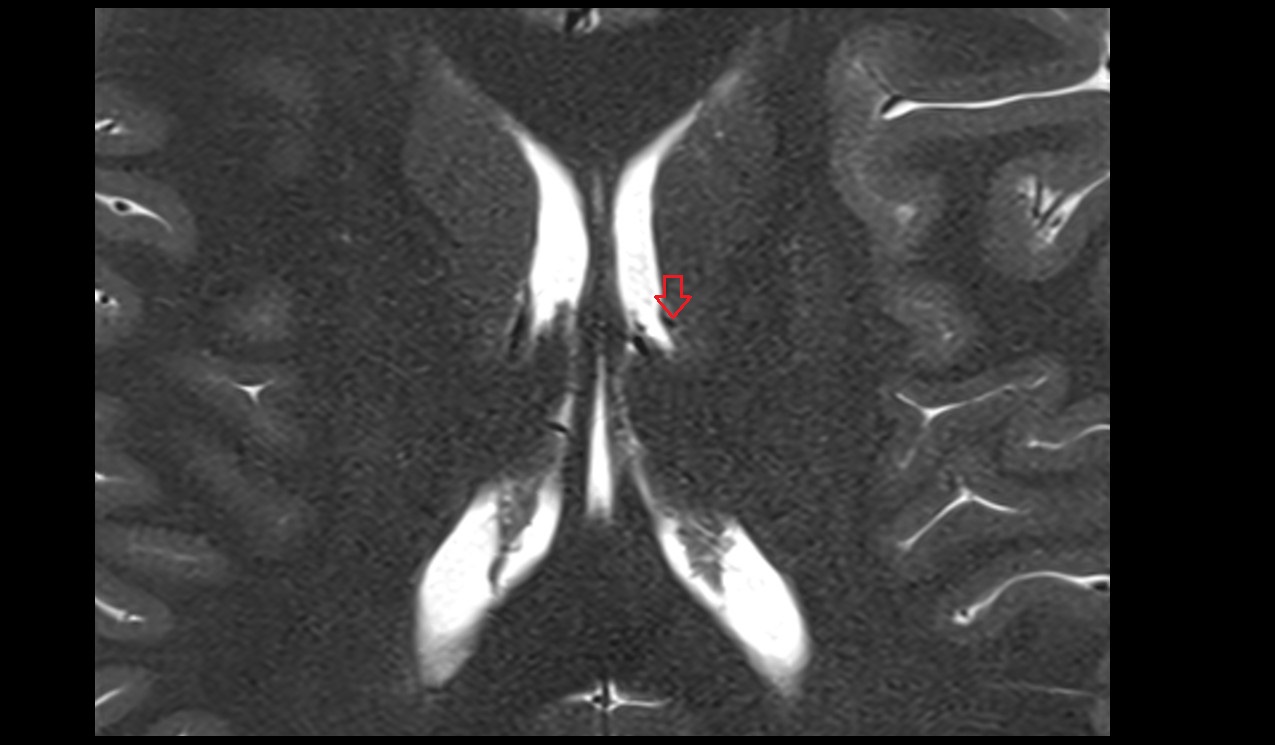

- Third ventricle

- Frontal horn of lateral ventricle

- Occipital horn of lateral ventricle

- Temporal horn of lateral ventricle